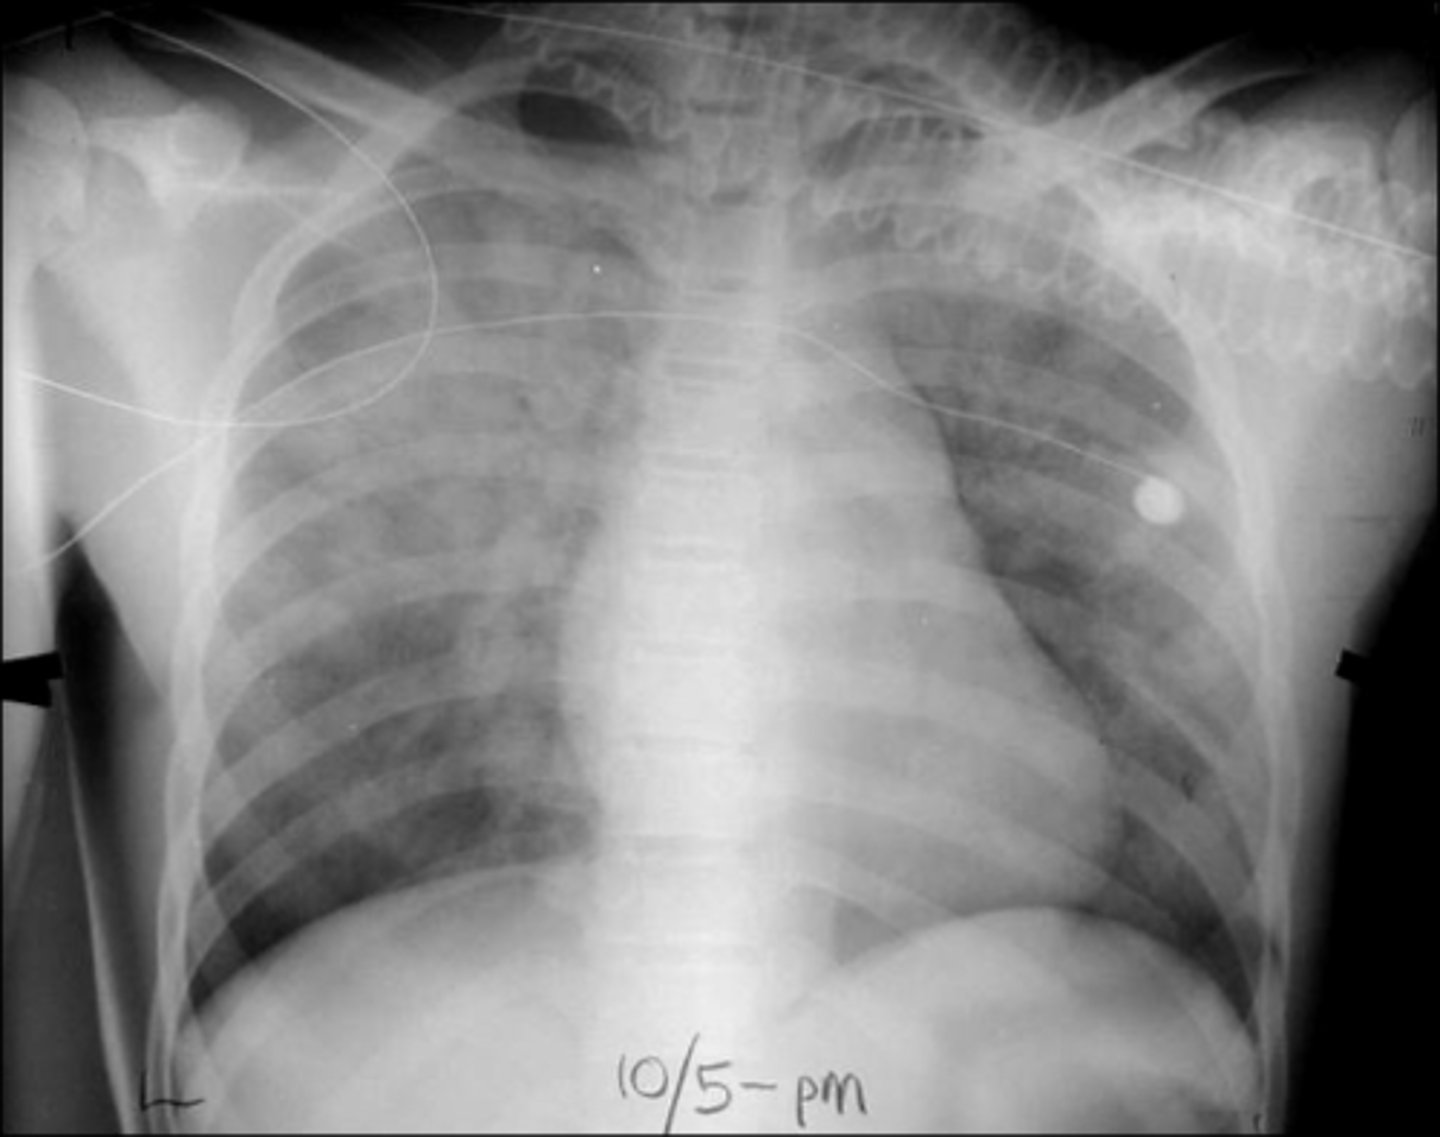

ARDS